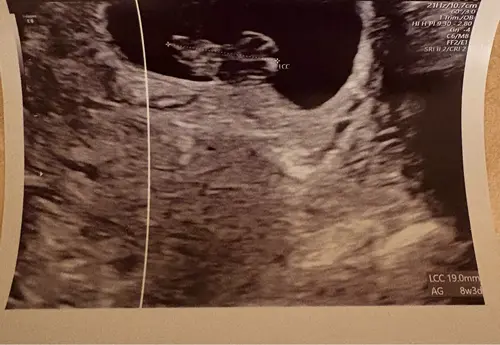

Heb je nog meer echo foto鈥檚, bij deze is het lastig te zien. Gaat er om hoe je kleine geloof ik in het vruchtzakje zit.

Deze beter misschien?